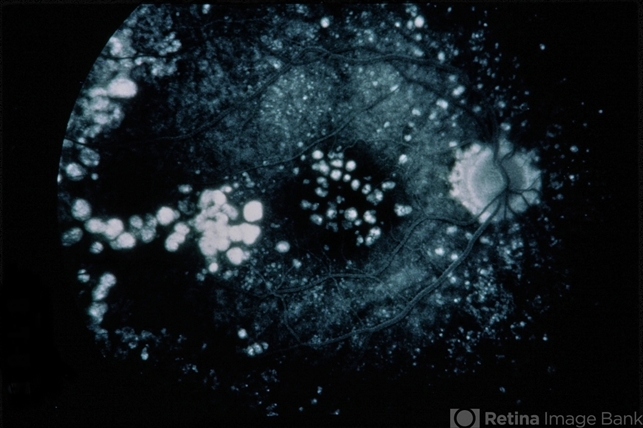

- Basal Laminar (Cuticular) Typical Drusen

- basal laminar drusen, cuticular drusen

- 42-year-old male patient with basal laminar (cuticular) / typical drusen.